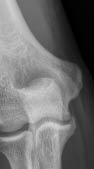

Given that the patient had engaged in sports and there was marked pain syndrome, ectomy of a fragment of the coronoid process was performed (Figure 4).

Fig. 4. Anterior–posterior radiograph of the left elbow joint after the surgery